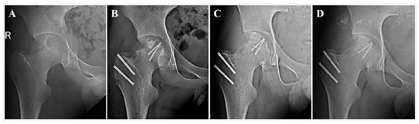

术后患者右髋关节疼痛明显缓解。术中病变组织送病理检查诊断为"软骨母细胞瘤合并动脉瘤样骨囊肿"(图4)。术后2周,患者去除支具,在下肢皮肤牵引辅助下行髋关节主、被动功能锻炼。术后2个月,髋关节功能恢复正常。术后4、7个月随诊复查X线片提示患者右侧股骨头形态轮廓、组织结构完整,植骨区愈合良好,右侧髋关节无发育畸形及右下肢生长阻滞(图5)。患者右髋关节功能活动正常,生活质量得到显著改善,保持随访持续观察远期疗效。